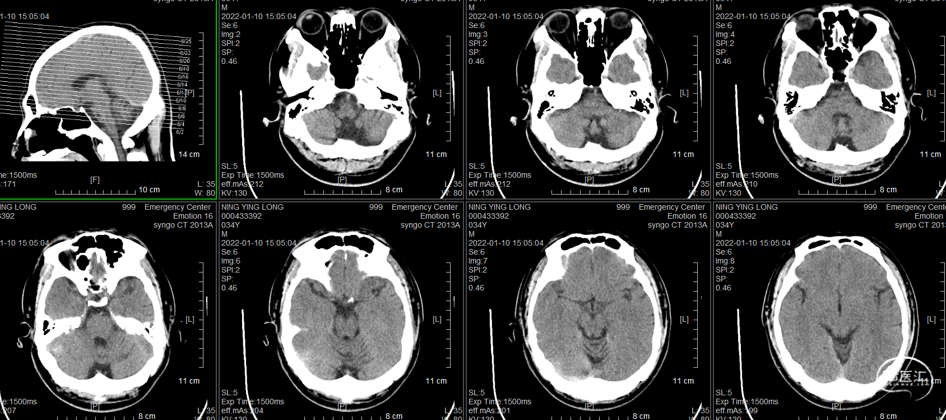

术后复查头颅CT(2022-1-15)

术后患者情况:

患者头痛消失,无不适主诉

1月21日复查腰椎穿刺,脑脊液压力230mmH20